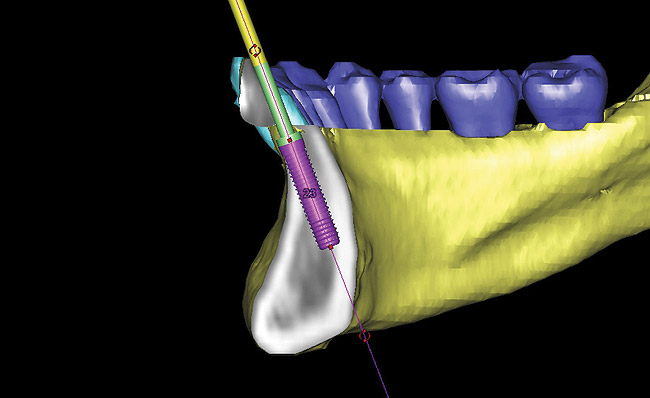

Figure 15  Presurgical 3-dimensional CT scan diagnostic planning for implant No. 23. Note the anticipated dehiscence at the facial aspect of the implant.

Figure 15

Figure 16  A cross-sectional view of postorthodontic site development at No. 23 position. Sufficient bone has been developed to accommodate implant placement in an optimal prosthetic position. Simultaneous GBR is planned at the coronal most portion of the implant per anticipated dehiscence.

Figure 16

Figure 17  Tooth-supported SurgiGuide (Materialise Dental, Leuven, Belgium) (2 mm level) in place.

Figure 17